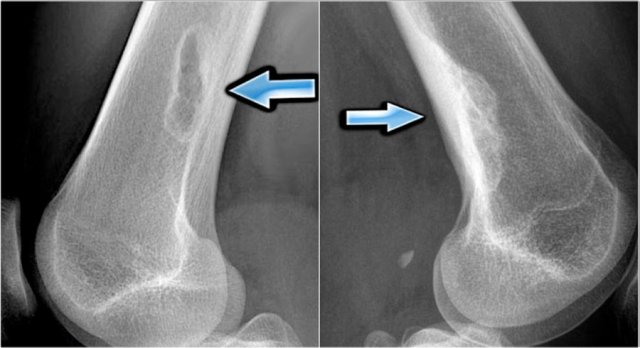

Osteoid osteoma Osteoid osteoma

Here the reactive sclerosis is the most obvious finding on the X-ray.

There is reactive sclerosis with a nidus that is barely visible on the radiograph (blue arrow), but clearly visible on the CT (red arrows).

CT scan is usually very helpful in detecting the nidus and differentiating osteoid osteoma from other sclerotic lesions like osteoblastoma, osteomyelitis, arthritis, stress fracture and enostosis.

MRI also may detect the nidus, combined with abundant bone marrow and soft tissue edema.